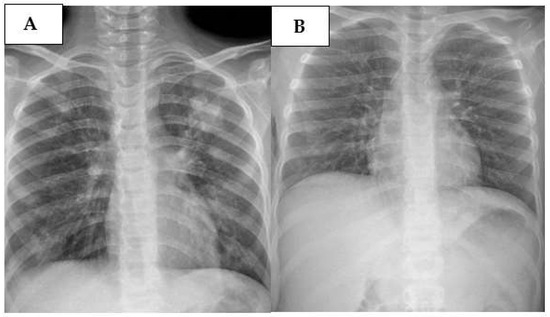

2.3. Cases 3 (UPN 1076952) and 4 (UPN 1077940)